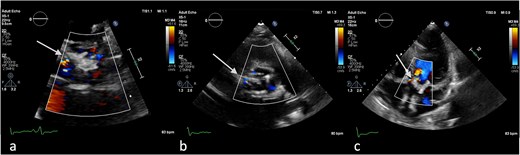

On the third day of hospitalization, transesophageal echocardiography revealed only moderate mitral regurgitation (Videos 3 and 4). However, on day 11, follow-up echocardiography showed a 7 × 18 mm vegetation on the prosthetic aortic valve, with a 5 × 7 mm floating formation (Fig. 2, Videos 5 and 6). By day 21, the vegetation had progressed, with a new formation on the tricuspid valve, an aortic annulus abscess, and worsened mitral regurgitation to severe (Figs 1 and 3, Videos 7 and 8). The development of double-sided endocarditis is very rare, and since the patient experienced it twice, congenital predisposing factors such as Patent Foramen Ovale and ventricular septal defects were ruled out. It was hypothesized that multiple predisposing factors ultimately led to the reinfection. Active IV drug use and its potential immunosuppressive effects, along with persistent poor dental condition and recurrent cutaneous infections, were identified as the main contributors, in addition to the patient’s overall non-adherence, for the development of double-sided endocarditis on two occasions.

(a) No vegetation, valve destruction of the prosthetic tricuspid valve on TTE RV inflow view, (b) No PVL of the prosthetic TV (TTE color doppler), (c) no signs of prosthetic IE on TV in TEE (day 21 of hospitalization).